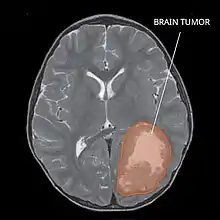

| Primitive neuroectodermal tumor of the central nervous system in a 5-year-old |

Several analysis can be used to determine the presence of the disease. Physical examinations showing papilledema, visual field defects, cranial nerves palsy, dysphasia, and focal neurological deficits are evidences for possible tumor.[2] PNETs can also be spotted through computed tomography (CT) and magnetic resonance imaging (MRI).[2] In images produced by MRIs, an irregular augmentation among a solid mass will indicated the presence of tumor.[3] However, the results of MRIs are usually ambiguous in defining the presence for this specific tumor.[2] In CT scans, the presence of PNETs will be indicated by an elevated density and an increase in volume of the brain.[2] The CT scan can also show calcification,[3] which is present in 41-44% of PNET cases.[2] Since the tumor can be replicated in other parts of the nervous system through the cerebrospinal fluid (CSF), a CSF analysis can also be conducted.[2] A spinal MRI is a fourth type of analysis that is useful in investigating the level of tumor propagation to the spinal cord.[2]